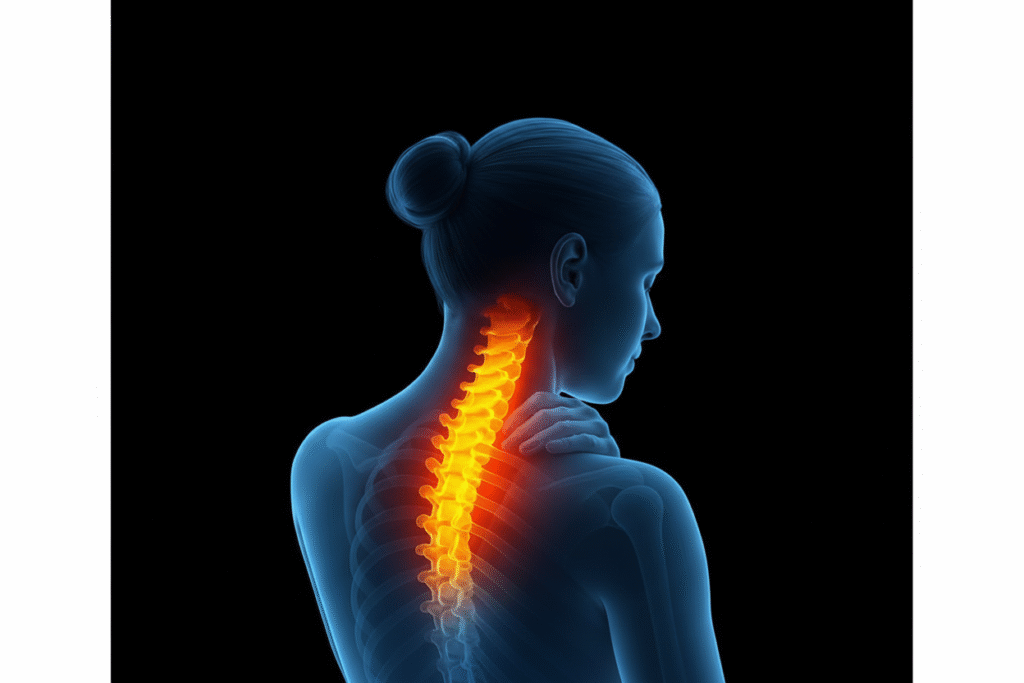

1. Cervical Spine Surgery

Cervical Spine Surgery is performed to treat conditions affecting the neck portion of the spine, such as herniated discs, spinal stenosis, degenerative disc disease, fractures, or cervical instability. The goal is to relieve pressure on the spinal cord and nerves, reduce pain, and restore mobility. Depending on the condition, procedures may include cervical discectomy, laminectomy, or spinal fusion. These surgeries can be done through traditional or minimally invasive techniques. Benefits include relief from neck and arm pain, improved nerve function, and better quality of life. Proper evaluation ensures safe, effective outcomes and long-term spinal stability.